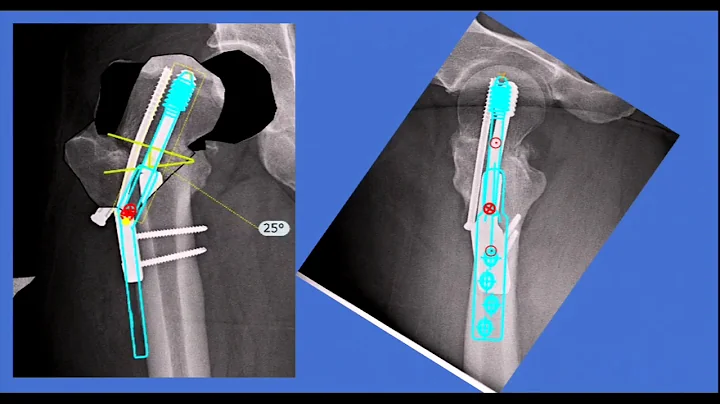

Hip fractures - Panel discussion

Drs. Christopher Haydel, Matthew Lorei, Drew Brady, and Kenneth Graf F...

• Duration:

9m 5s